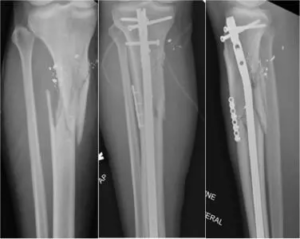

Plate-assisted reduction during intramedullary nailing of tibia shaft fractures may lower risk of nonunion or infection: Study

Plate-assisted reduction during intramedullary nailing of tibia…